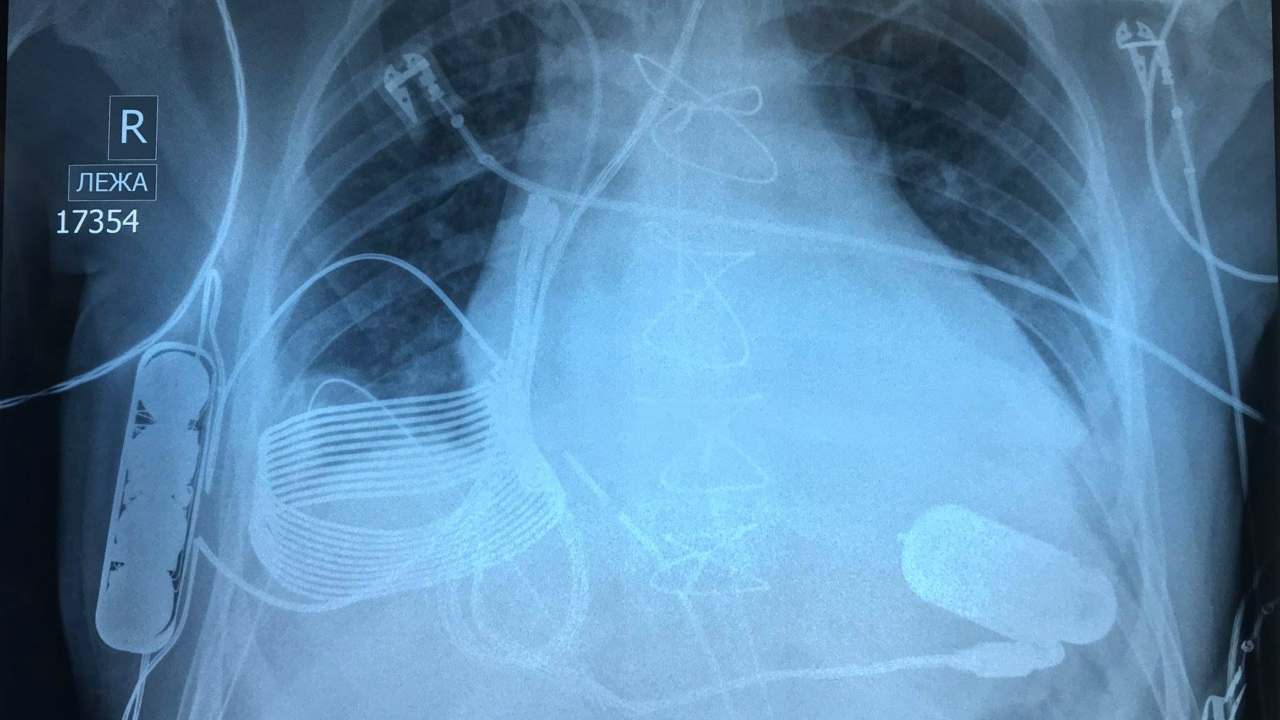

since the first mechanical heart pump — the ventricular assist device — was implanted into a patient whose heart couldn’t pump on its own. Countless lives have been saved by the device since then. One of those patients is a 24-year-old man, Ismail Turnsunov, who was implanted with a heart pump a few weeks ago after being rushed into the hospital with end-stage heart failure. What makes this implant unique is how the device charges up. It requires no wires or charging ports to be connected directly, and can be charged wirelessly. With this feature alone, the device eliminates one of the biggest drawbacks of VADs, which mean an instant heart attack if it fails a patient. [caption id=“attachment_6077901” align=“alignnone” width=“1280”]

The three-part bionic heart implant in an X-ray. Image credit: Facebook/Leviticus Cardio[/caption] Usually, a VAD needs to be plugged into a power outlet or an external battery via a hole in the patient’s abdomen. It is absolutely necessary for all patients fitted with a heart pump to carry an extra pair of batteries in case one runs out of power. Another major drawback is the exposed hole through which the power cord runs out of the body — an unsafe, risky gateway for infections. Patients have to alert and be attentive to every little symptom to run to a specialist at the drop of a hat. But Turnsunov’s implant doesn’t require a power cord at all. It uses a wireless charging system built by Israeli technology company Leviticus Cardio.

The instrument has an inductive coil, battery, and an internal controller, which are all implanted into Turnsunov’s chest. The device can stay powered for roughly eight hours from a single charge. When it needs to be recharged, Turnsunov has to put on a vest which has a built-in external device and coil to charge the inner coil using an electromagnetic field. The device comes with a wrist monitor for Turnsunov to track his VAD and battery. In case something in the wireless charging system fails, there currently isn’t a back-up wired option. However, the patient hasn’t needed to use it since his surgery several weeks ago.